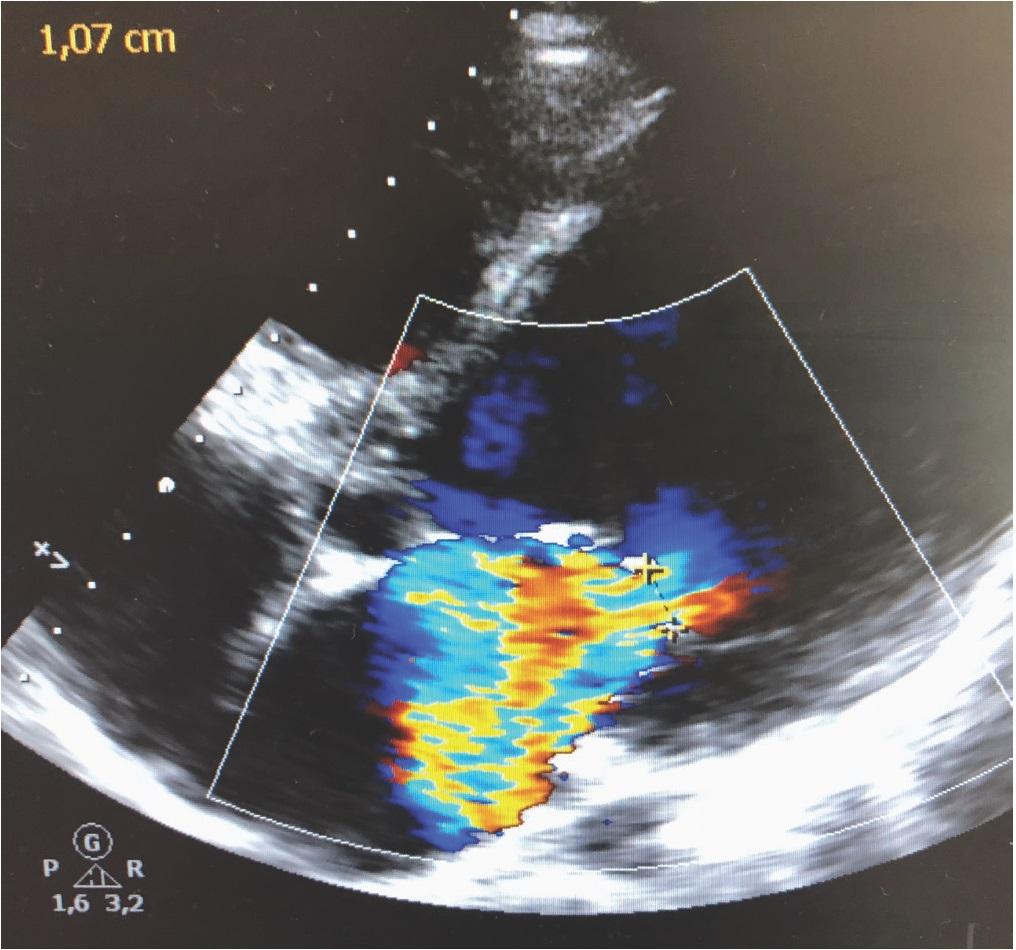

Transesophageal echocardiography (TEE) confirmed posterior papillary muscle rupture, with severe mitral regurgitation and severe LV dysfunction (Figure 1).

Figure 1